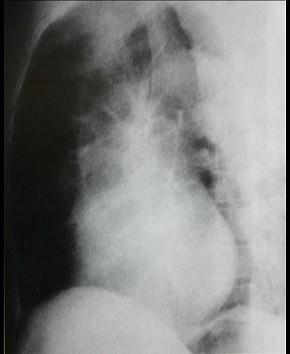

对如下心脏左侧位片描述正确的是 ( )A、正常心脏B、以上均错C、左心房Ⅱ度增大D、右心室增大E、左心室增大

选项 A、正常心脏 B、以上均错 C、左心房Ⅱ度增大 D、右心室增大 E、左心室增大

答案 E